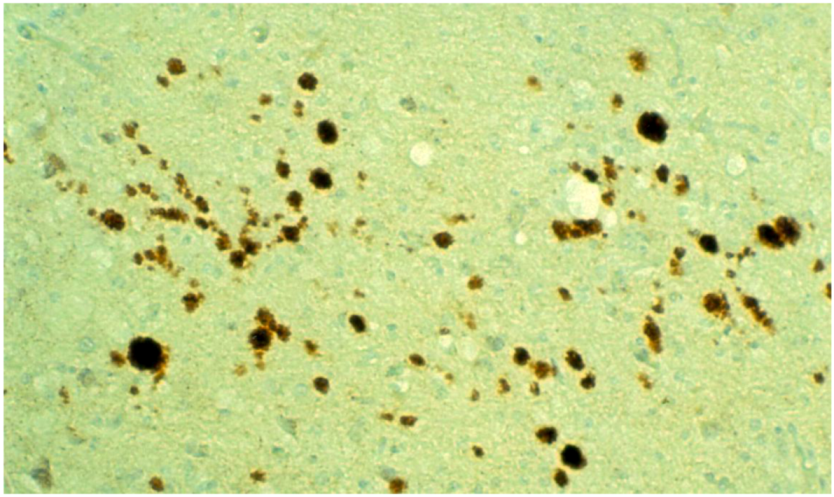

8. Neuropathology